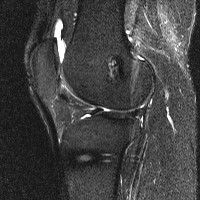

안녕하세요 8년전 십자인대 수술하고 최근 무리한 운동에 무릎 불편감이 생겨서

mri 찍었습니다.

진단결과는 첫 찍은 병원에서 활액막염 이라는 진단을 받았습니다. 혹시 봐주실 수 있으실까요?

올라온 MRI가 단편적이라서 정확한 진단에 어려움이 있지만 십자인대에는 큰 이상이 있지는 않은것 같으며, 무릎관절내 물이 있는 것으로 보아 활액막염의 진단이 맞을 것 같습니다.

하지만 단편적인 영상이기 때문에 촬영병원에서 정확한 판독지 등을 받으시는 것이 좋겠습니다.